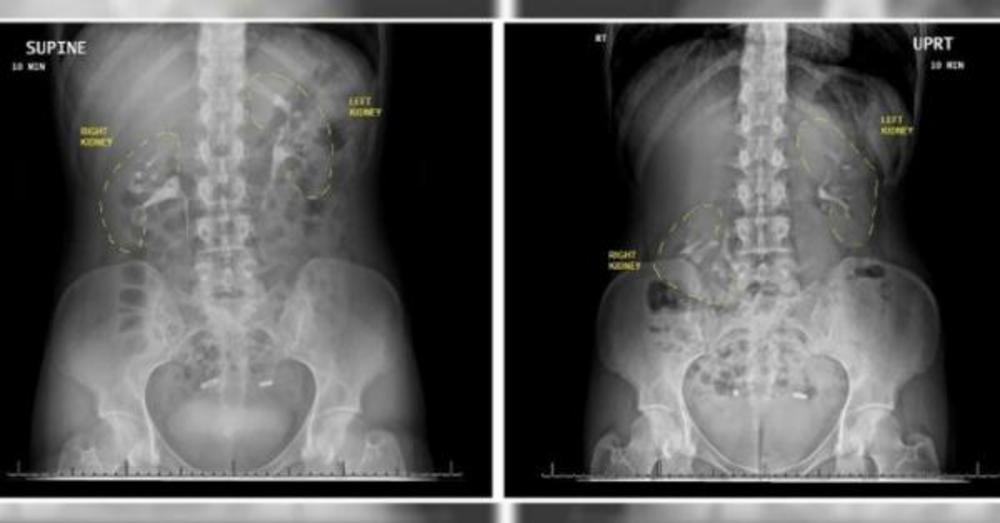

Žena je, naime, imala „lutajući bubreg“, odnosno nefroptozu, stanje u kome jedan od bubrega upadne u karlicu kada osoba ustane. Kod ove žene u pitanju je bio desni bubreg koji je stalno propadao više od šest centimetara.

– Kada se ovo dogodi, dešava se da i krvni sudovi koji su zakačeni za organ počnu da se krive, a krivi se i mokraćovod koji prenosi urin iz bubrega do bešike. Zbog tog savijanja, urin ne može da se sasvim izbaci i vraća se u bubreg, zbog čega se on naduje i počinje da boli – objašnjava dr Aškaj Sud, urolog u bolnici Henri Ford u Detroitu koji je i pomogao ovoj ženi.

– Jako je teško dijagnostikovati lutajući bubreg, inače vrlo retko stanje, uglavnom zato što, kada se radi snimanje, osoba leži pa je bubreg na svom mestu, pa lekari ni ne posumnjaju da tu leži problem – objašnjava on.